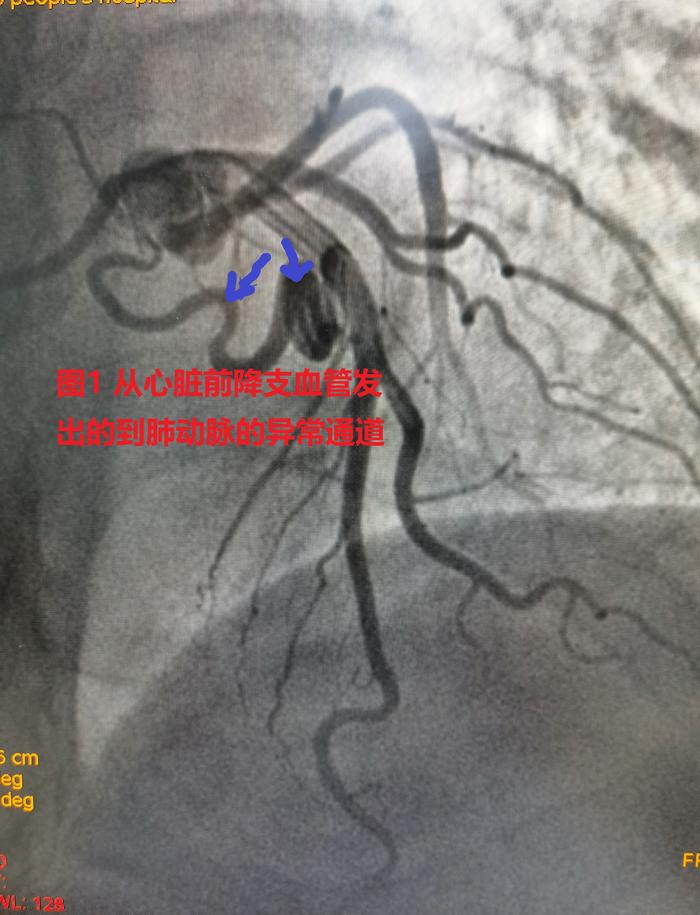

冠状动脉肺动脉瘘!_冠状动静脉瘘_介绍_症状表现 - 好大夫在线

冠状动脉肺动脉瘘!